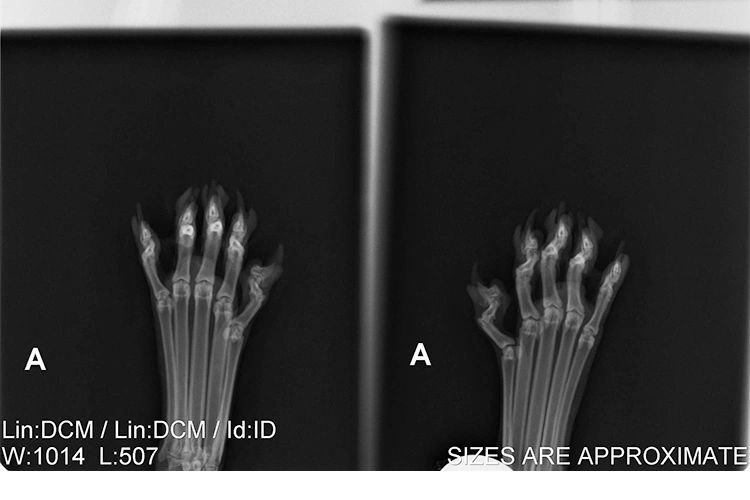

Arrows indicate pathology to distal p2 cartilage. KCPP now routinely X-rays the paws of all declawed cats.

. Declaw Salvage Radiographs of declawed cat paws These radiographs x-rays were acquired using a oblique dorsal-palmar angle. The x-ray on the left is of a declawed cats paw. The joints in their.

The x-ray on the left is of a declawed cats paw. A digital dental sensor was used because of its high. The price ranges from 150 250 depending on the type of x-ray machine that is used and.

According to one study 42 of declawed cats experience long-term pain and around a quarter of declawed cats hobble. A declaw is an amputation and not always a complete one. The x-ray on the left is.

Declawed Cat Paw X Ray. I havehad 3 cats that were declawed plus another cat of my neighbors all front paw only. The one on the right is a of a cat with intact claws.

Doub has been researching declawed cats by taking x-rays of their paws. The one on the right is a of a cat with intact claws. The cats gait changes as weight is shifted backward from the toes to the large rear pad of the paw.

Oct 25 2015 - The x-ray on the left is of a declawed cats paw. 33 Of cats suffer at least one behavioral problem after declaw surgery.